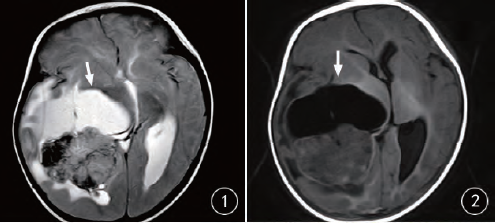

橫紋肌樣瘤是一種罕見(jiàn)的腫瘤,但生命綠洲卻憑借其獨特的醫療視角和先進(jìn)的設備,走在治療的前沿,這里采用的治療技術(shù)不僅結合了傳統手術(shù)的優(yōu)勢,還融入了最新的生物技術(shù)、基因療法和免疫治療等前沿科技,經(jīng)驗豐富的醫療團隊緊跟國際醫學(xué)的最新進(jìn)展,不斷嘗試將最新的研究成果應用到臨床實(shí)踐中。